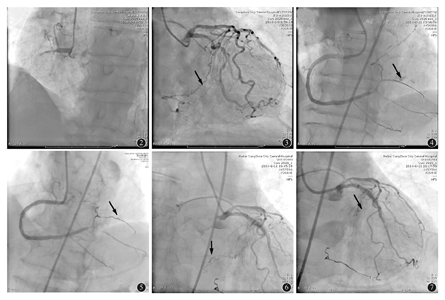

患者男性,76岁,因"阵发性胸痛5个月"于2014年6月10日入院。患者5个月来快步行走时发生胸痛,位于心前区,手掌大小,程度较剧烈,尚能忍受,伴出汗,无放射痛,持续3~5 min,休息后缓解。既往高血压病史10余年,未正规服药,血压最高达170/100 mmHg,控制不理想,无家族史。入院查体:血压150/70 mmHg,双肺呼吸音清,心率56次/min,律齐,未闻及杂音。心电图示窦性心律,Ⅲ、aVF导联T波倒置(图1)。入院诊断:冠心病 稳定型劳累性心绞痛,心功能1级,高血压2级。给予阿司匹林100 mg和氯吡格雷75 mg双联抗血小板治疗。冠状动脉造影示左主干正常,右冠状动脉近端完全闭塞(图2),为慢性完全闭塞病变,左前降支近中段斑块,左回旋支正常,向右冠状动脉提供Ⅲ级侧支(图3)。拟行右冠状动脉介入治疗。经右股动脉7FAL1.0指引导管送至右冠状动脉开口,在Finecross130微导管支撑下,Field Fc、XT、U3导丝均不能进入右冠状动脉血管真腔,遂采用逆向导丝技术,经右桡动脉7FEBU3.75指引导管送至左冠状动脉开口,Sion导丝通过LCX-侧支循环-右冠状动脉后侧支将Finecross150微导管送至右冠状动脉,应用反向Cart技术导丝逆向送至右冠状动脉开口进入指引导管内,送入微导管,应用RG3导丝,应用1.25 mm×15.00 mm及2.0 mm×15.0 mm Ryujin球囊前向扩张右冠状动脉闭塞段,于右冠状动脉病变处成功串联置入2.75 mm×38.00 mm、3.0 mm×38.0 mm、3.5 mm×22.0 mm Helios支架,造影显示右冠状动脉粗大,TIMI血流3级,但远端后侧支发生EllisⅡ型穿孔(图4),考虑导丝所致,应用1.5 mm×15.0 mm Ryujin球囊封堵约15 min,造影无对比剂外渗,患者生命体征平稳,返回病房。返回病房后半小时,患者出现胸闷气短,恶心呕吐,测血压80/50 mmHg,心率40次/min,急查床旁超声心动图示心包积液,积液最深处14 mm,紧急心包穿刺,引流出血性液体300 ml,患者症状好转,血压恢复,于导管室复查冠状动脉造影,显示右冠状动脉远端后侧支血管侧壁对比剂外渗,应用COOK18S3/2 mm微型弹簧圈封堵(图5),观察半小时无对比剂渗出,再次返回病房。1 h后患者再次出现心包压塞症状,再次复查冠状动脉造影显示右冠状动脉管腔通畅,TIMI血流3级,左回旋支至右冠状动脉侧支循环分支末梢对比剂渗出(图6),予以微导管内注射50 U凝血酶于左回旋支血管,无效,弹簧圈封堵左回旋支侧支近端(图7),观察1 h,冠状动脉造影示左回旋支侧支血管消失,无对比剂外渗,封堵成功。24 h后复查超声心动图,无心包积液,撤出引流管。患者病情平稳,1周后痊愈出院,1个月后复查,患者无不适。